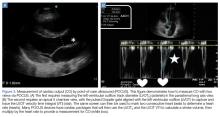

Figure 3.

In the most basic applications, POCUS provides direct visualization of a patient’s cardiac function, presence or absence of lung sliding to suggest a pneumothorax, presence of pulmonary edema, assessment of CVP pressures or potential for fluid responsiveness, as well as identification of potential thoracic, peritoneal, or pelvic cavity fluid accumulation that may suggest hemorrhage. There is literature to support that these assessments performed by the EP have been shown to be comparable to those of cardiologists.59,60 With continued practice and additional training, it is possible for EPs to even perform more “advanced” hemodynamic assessments to both diagnose and guide therapy to patients in shock (Figures 3 and 4).61